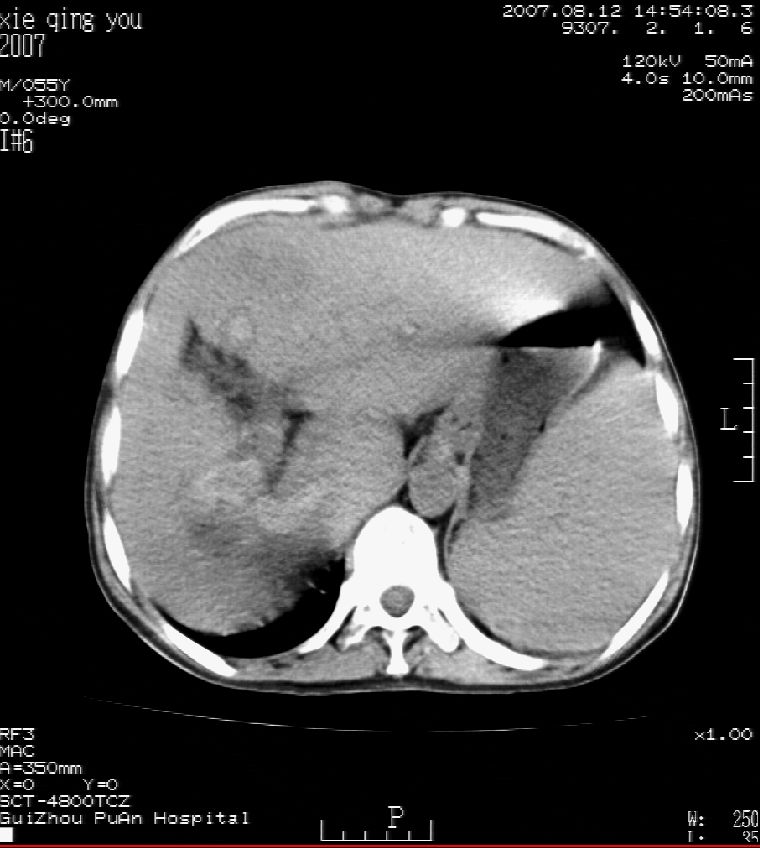

男 55岁  反复上腹痛1年,伴恶心呕吐。2005年做第一次检查后,到外院做b超检查提示肝囊肿,未做任何手术。2006年做过胆总管结石术。骨窗未见异常

2007年8月片

这个病灶很有意思,怎么可能没有了呢?我考虑当时很可能是肝脏脓肿(b超示囊肿是有可能误诊的,因为影像表现都是低回声吗?),现在脓肿吸收了,肝脏萎缩,肝裂增宽了.别的肝叶代偿增大,不过现在左内叶的确有个占位,肝内多发结石,脾脏比以前大,不排除有肝硬化可能.建议增强扫描给于定性!!!!

肝硬化\\脾大,肝左叶肝癌可能性大,建议增强扫描.肝内胆管多发性结石.

1, 肝硬化,脾大;2,肝左叶肝癌可能性大,建议增强扫描.3,肝内胆管多发性结石.

考虑肝内胆管多发结石引起的肝内局部炎症,这样可以解释2005年肝右叶病灶的吸收和左叶新病灶.

肝硬化、脾大、肝内胆管多发结石。肝左叶低密度占位。建议增强扫描.排除肝癌